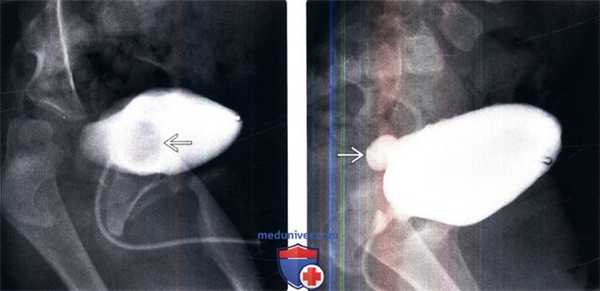

(Слева) МЦУГ в прямой косой проекции: у младенца мужского пола с анамнезом инфекции мочевыделительных путей определяется округлый дефект наполнения мочевого пузыря с гладкой поверхностью. Эти признаки характерны для уретероцеле.

(Справа) После дальнейшего растяжения мочевого пузыря уретероцеле вывернулось наружу из просвета мочевого пузыря. Выворот уретероцеле можно ошибочно принять за дивертикул мочевого пузыря.

(Слева) КТ мочевого пузыря без контрастирования, аксиальный срез: два плотных кальцинированных конкремента в области левого МПС.

(Справа) Аксиальная проекция того же среза, полученная в отсроченную урографическую фазу: конкременты находятся внутри уретероцеле. Иногда дифференциальная диагностика между врожденным уретероцеле, содержащим камни и приобретенным расширением терминального отдела мочеточника при обструкции конкрементом (так называемое «певдоуретероцеле») может представлять трудность.